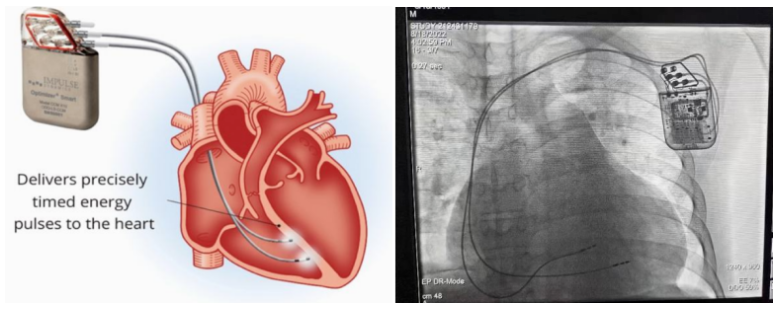

①植入式心臟復(fù)律除顫器

Implantable Cardioverter Defibrillator,ICD

植入式心臟復(fù)律除顫器是一種具有除顫功能的高級(jí)起搏器,是一種體積小、能植入患者胸部皮下組織的醫(yī)療設(shè)備。慢性心衰患者易發(fā)生室性心動(dòng)過(guò)速或心室顫動(dòng),導(dǎo)致心源性猝死(SCD)。ICD 則能在幾秒內(nèi)自動(dòng)識(shí)別并治療快速室性心律失常,通過(guò)低能量心臟轉(zhuǎn)復(fù)和高能量除顫等功能,顯著降低惡性室性心律失常引起的猝死風(fēng)險(xiǎn)??杉皶r(shí)自動(dòng)為患者轉(zhuǎn)復(fù)心律,通俗地說(shuō)就是裝在體內(nèi)的自動(dòng)除顫儀。